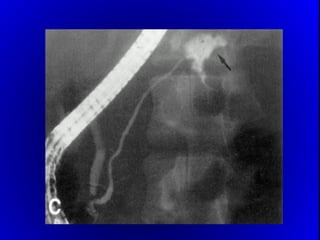

1.- FISTULOGRAMA:

 7 A 10 DIAS DE INICIADA LA FÍSTULA

 DA EL DIAGNÓSTICO ANATÓMICO.

 PRONOSTICA EL CIERRE ESPONTÁNEO O NO

2.- ECOGRAFÍA , T.A.C.

-ABSCESO INTRABDOMINAL.

-DRENAJE PERCUTÁNEO